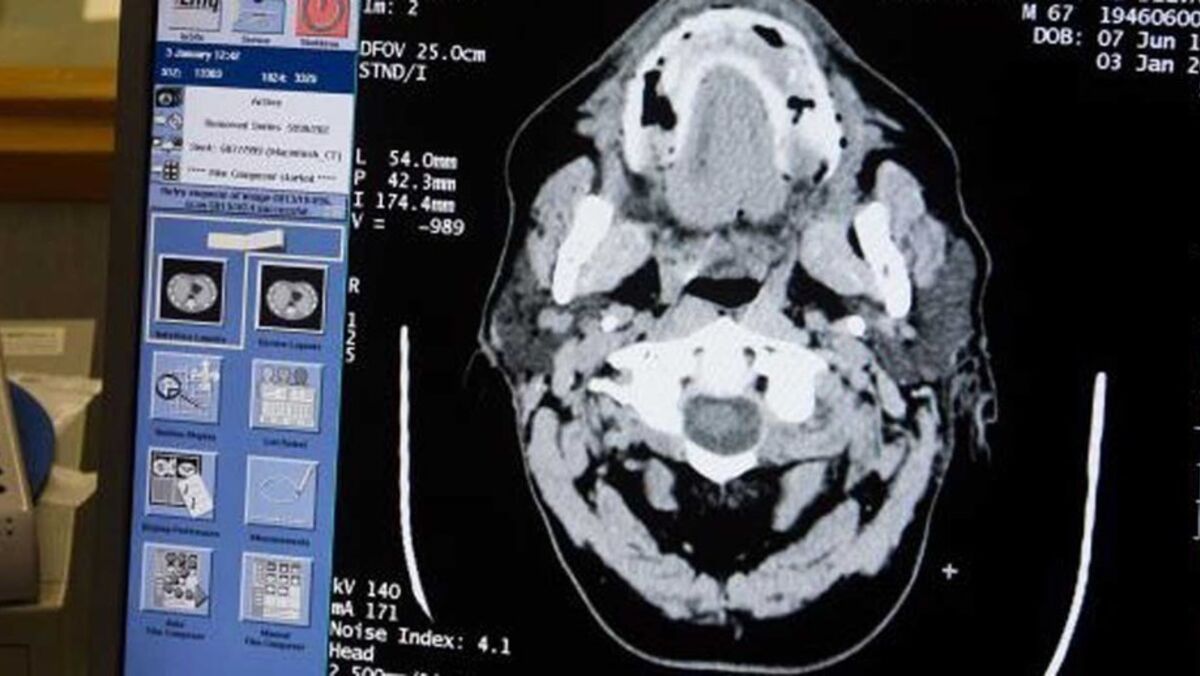

A Federação Inglesa de Futebol (FA) pretende diminuir os riscos de doenças degenerativas no cérebro provocadas pelos sistemáticos cabeceamentos, pelo que vai proibir, provisoriamente, este gesto técnico nos jogos sub-12, para posteriormente os tornar definitivos.

Vários estudos têm relacionado os cabeceamentos na bola com uma maior tendência de sofrer doenças degenerativas no cérebro: no caso dos futebolistas profissionais, os riscos são três vezes e meia superiores ao cidadão comum.

Nos últimos anos, os campeões do mundo pela Inglaterra em 1996, Nobby Stiles e Jack Charlton - irmão de Bobby Charlton, que padece de demência -, faleceram devido a doenças degenerativas supostamente relacionadas com os repetidos 'golpes' de cabeça durante a carreira de futebolista.